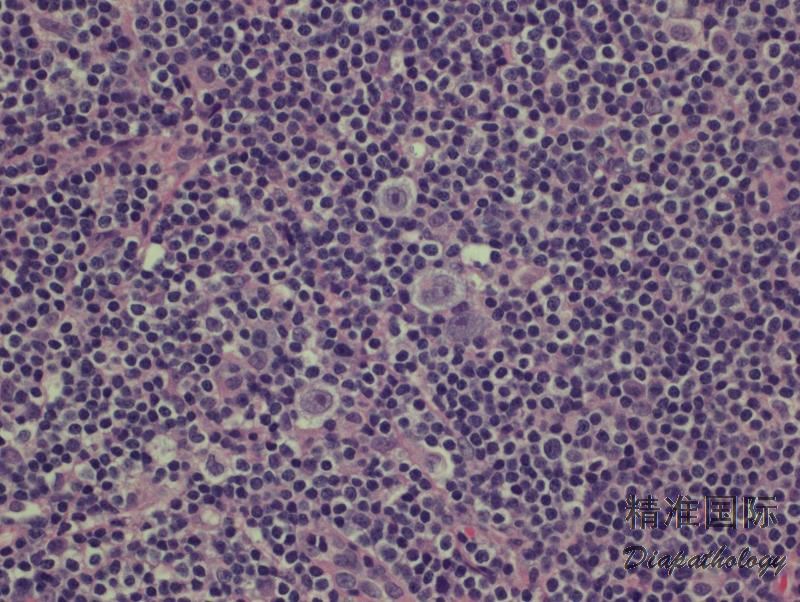

有两种生长模式:结节型和弥漫型。绝大多数病例呈结节型生长,结节为扩大的套区,有时可见偏心的生发中心。典型的 HRS 细胞散在分布结节中,有时肿瘤细胞类 LP 细胞。粒细胞和嗜酸细胞罕见(结节之间)或缺如。无纤维化。少数病例背景淋巴细胞呈现弥漫生长模式,常混有组织细胞。

免疫组化:肿瘤细胞 CD30+,CD15+/-,PAX5+,MUM-1+,CD20-/+,OCT2-/+,BOB1-/+,EBER+(40%),CD79a- ,CD45-,EMA-,ALK-。背景细胞表达全 B 抗原,但弥漫型可有大量 T 细胞。部分病例可见 T 细胞环绕 HRS 细胞。

肿瘤细胞 CD30+,CD15+/-,PAX5+,MUM-1+,CD20-/+,OCT2-/+,BOB1-/+,EBER+(40%),CD79a-,CD45-,EMA-,ALK-。背景细胞表达全 B 抗原,但弥漫型有大量 T 细胞。